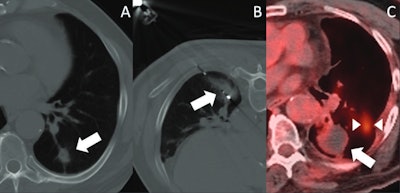

Images depict post-SBRT image-guided thermal ablation. (A) Axial CT image demonstrates a nodular recurrence of NSCLC at the site of prior SBRT in the left lower lobe (arrow). (B) Intraprocedural axial CT image shows placement of a microwave ablation probe within the recurrent tumor, with surrounding ground-glass opacity (arrow). (C) PET-CT obtained 14 months post-ablation demonstrates no significant FDG uptake within the treated lesion (arrow); however, a new site of disease is noted (between arrowheads).Images depict post-SBRT image-guided thermal ablation. (A) Axial CT image demonstrates a nodular recurrence of NSCLC at the site of prior SBRT in the left lower lobe (arrow). (B) Intraprocedural axial CT image shows placement of a microwave ablation probe within the recurrent tumor, with surrounding ground-glass opacity (arrow). (C) PET-CT obtained 14 months post-ablation demonstrates no significant FDG uptake within the treated lesion (arrow); however, a new site of disease is noted (between arrowheads).ARRS